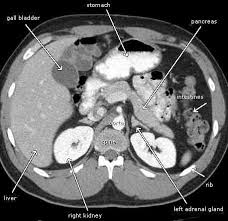

Kidney Tumor On Ct Scan. He also sent me for ct scan to get a clearer view turns out they spotted something on a kidney. Some patients however may need a biopsy.

He also sent me for ct scan to get a clearer view turns out they spotted something on a kidney. Typically these are detected incidentally in other words the patient has a scan for an unrelated problem and a tumor in the kidney is found. It this were indeed a kidney cancer it would be nearly impossible for it to have spread at that size.

Not all growths on. Kidney tumor contained within the kidney small kidney tumor 4cm increasingly we are detecting these small kidney tumors due to the increased use of ultrasound ct scan and mri. It this were indeed a kidney cancer it would be nearly impossible for it to have spread at that size. On imaging they have a variety of radiographic appearances from solid and.